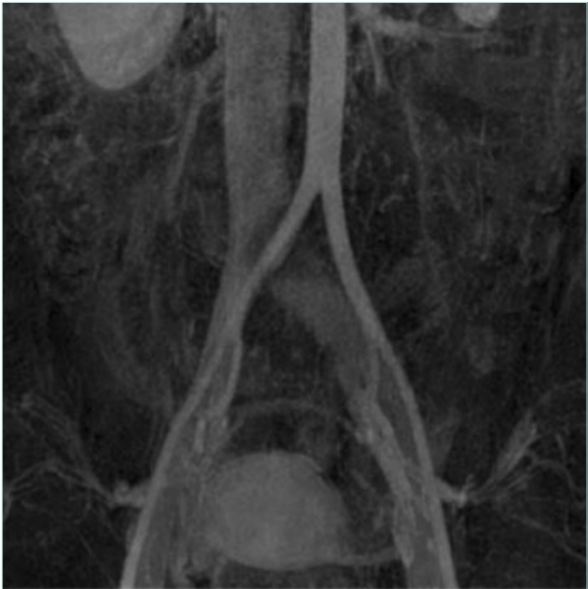

CTV and MRV are second-level diagnostic tools in case of suspected MTS and offer complete examination of the venous system that can also be enhanced by 3D reconstruction. CTV has some disadvantages related to radiation exposure and iodinated contrast, but it’s well recognized that it provides high-quality studies and a complete evaluation of the venous anatomy. MRV is the most versatile imaging, with dynamic sequences that can provide information regarding velocity and volume while providing high-quality morphologic images of the compressed vein such as with fibrotic scarring, postthrombotic fibrosis, as well as collaterals and varicose veins (Figure 1).11,12

Venography